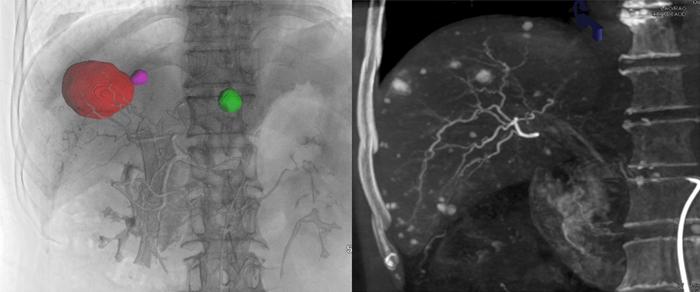

Interventional therapies, including transarterial chemoembolization (TACE), yttrium-90 selective internal radiation therapy ( 90 Y SIRT), and ablation, are pivotal in treating liver malignancies. These interventions are commonly guided by imaging techniques such as digital subtraction angiography (DSA), computed tomography (CT), ultrasonography, or magnetic resonance imaging. Nonetheless, each imaging modality has inherent limitations. DSA, for instance, provides two-dimensional images of blood vessels and tumor staining, which may fall short of specific procedures. Ultrasonography struggles with visualizing small lesions and those near the diaphragm, while CT lacks real-time imaging capabilities.

Cone-beam computed tomography (CBCT), a volumetric imaging technique utilizing a cone-shaped X-ray beam, offers a promising alternative. It facilitates automatic detection and navigation of target vessels, fluoroscopy, and post-TACE embolization assessment, potentially overcoming some limitations of traditional imaging methods. Despite its recognized importance in liver malignancy interventions, CBCT's integration into clinical practice faces challenges such as limited awareness among interventional radiologists, inconsistent parameter standardization, and restricted application areas. To address these issues, the Chinese College of Interventionalists has issued a consensus statement to standardize and promote CBCT use in liver malignancy therapies. This statement, grounded in evidence-based practices and clinical expertise, has been registered on the International Practice Guidelines Registration and Transparency Platform (http://www.guidelines-registry.cn/index, Registration number: PREPARE-2023CN980).

The consensus outlines CBCT scanning techniques, operational standards, and clinical applications while addressing its challenges, including limited soft tissue contrast, radiation exposure, image artifacts, resolution constraints, and a narrow field of view. Despite these hurdles, CBCT’s future is bright, with anticipated advancements in detector resolution, reconstruction algorithms, and multimodal imaging integration. Innovations aimed at reducing radiation doses, enhancing real-time imaging, and incorporating artificial intelligence are expected to refine CBCT’s accuracy and safety, solidifying its role in the interventional management of liver malignancies.